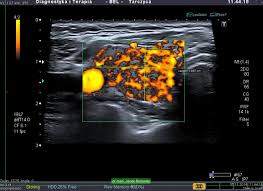

Guzki Tarczycy Czy Guzki Tarczycy Sa Grozne

Guzki Tarczycy Czy Guzki Tarczycy Sa Grozne from www.medicover.pl